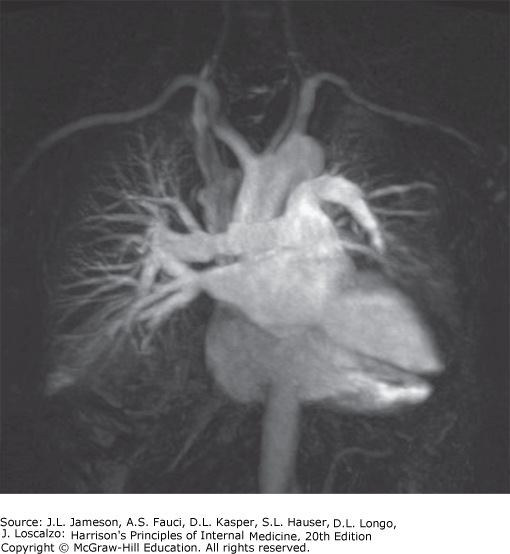

| 11 | Be familiar with diagnostic procedures in respiratory disease | Diagnostic modalities include imaging (chest X-ray, CT/helical CT, MRI, ultrasound, nuclear medicine/V-Q scan, PET scan, virtual bronchoscopy) and tissue-sampling techniques. CT is superior to plain film for mediastinal disease, emphysema characterization, and lung cancer staging. MRI excels at vascular assessment without contrast. |

| MRI | No ionizing radiation. Distinguishes vascular from nonvascular structures without contrast (flowing blood = no signal). Poorer spatial resolution and parenchymal detail than CT | Vascular abnormalities (PE, aortic aneurysm/dissection), when CT contrast is contraindicated |

| Pulmonary Angiography | Catheter placed in pulmonary artery, radiopaque contrast injected. Demonstrates filling defects or abrupt vessel cutoff from intravascular thrombus | Pulmonary embolism diagnosis, arteriovenous malformation visualization, neoplastic PA invasion assessment |